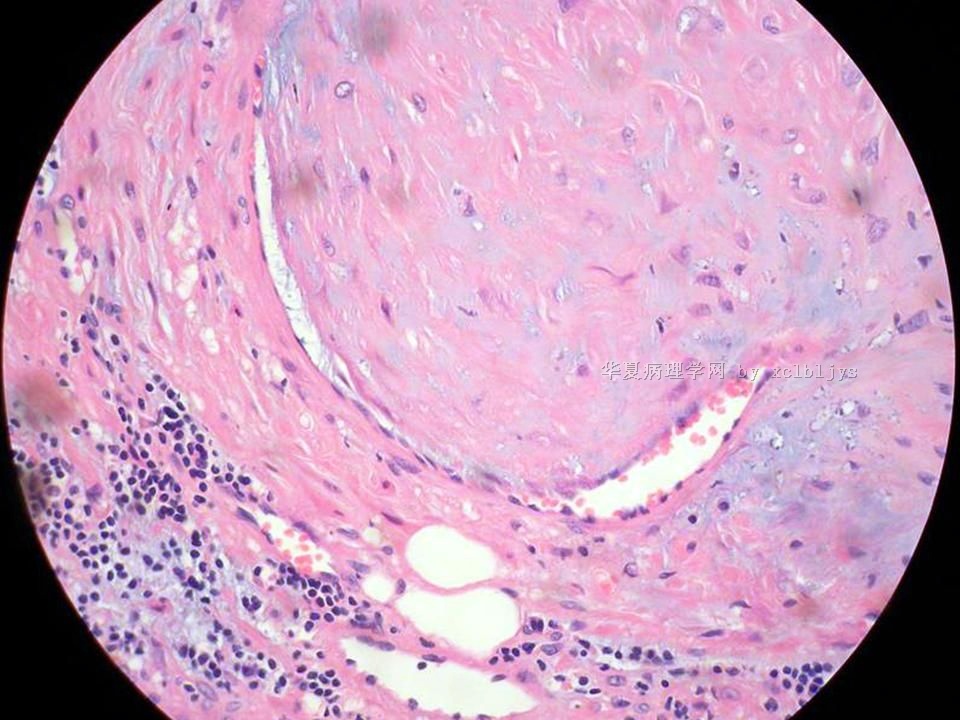

| 以下是引用xclbljys在2010-12-22 17:20:00的发言: 本例我们科室医生有两种意见:一种是炎性假瘤;第二种意见是炎性假瘤伴局限性Wegener肉芽肿。 依据是眼眶内肿块含有大量的动脉内膜炎改变,浸润的炎细胞有淋巴细胞、浆细胞、嗜中性粒细胞和嗜酸细胞等,如图16所示,炎细胞已经浸润动脉壁全层,应符合坏死性小动脉炎,但尚不能确定动脉壁弹力纤维层的破坏。 请各位老师点评! Wegener肉芽肿多发生在上呼吸道、肺、肾脏和皮肤等器官与组织。坏死性血管炎需证实有纤维素样坏死。小动脉炎多在皮肤病变比较明显。本例的小动脉炎或许是炎症引起的继发性改变。需要完善病史,查血免疫指标,看有没有系统性疾病。如果没有系统性疾病,还是考虑慢性炎症继发小血管炎。

血管炎是正常营养/供给血管的炎症性病变,而不是增生血管的炎症。血管炎往往有明显的临床相应症状,如皮疹。典型的Wegerner肉芽肿病有三联症(上呼吸道、肺、肾脏病变)。血管炎不仅是有炎症细胞,同时有血管壁的变性、坏死(纤维素样), 内皮细胞的变质和增生,炎症细胞浸润(包括中性粒细胞、淋巴细胞、组织细胞、嗜酸性细胞、巨细胞等)。不同类型的血管炎累及的血管大小、炎症细胞的类型、有无肉芽肿改变都不相同。血管炎的病因可以是过敏、自身免疫、胶原性疾病、感染等多种因素。